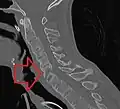

Fracture of the T5 and C7 vertebra due to trauma in a person with ankylosing spondylitis as seen on a CT scan